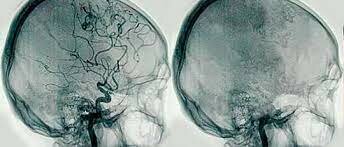

Evento 4 Aplicaciones desde 1895 hasta nuestros días de la radiación ionizante

El neurólogo portugués Egas Moniz, desarrolló la angiografia para diagnosticar transtornos cerebrales